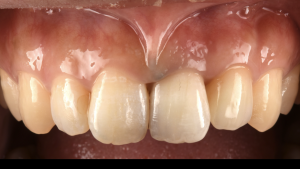

土台ごと折れた前歯をインプラントで治療した症例【前歯部審美症例12】

初診時。前歯がグラつくとのことでご来院されました。詳しく調べてみると、かぶせと土台が根っこごと折れてしまっている状態でした。非常に太い土台が入っていたことにより、根が折れやすい状態だったと予想できます…